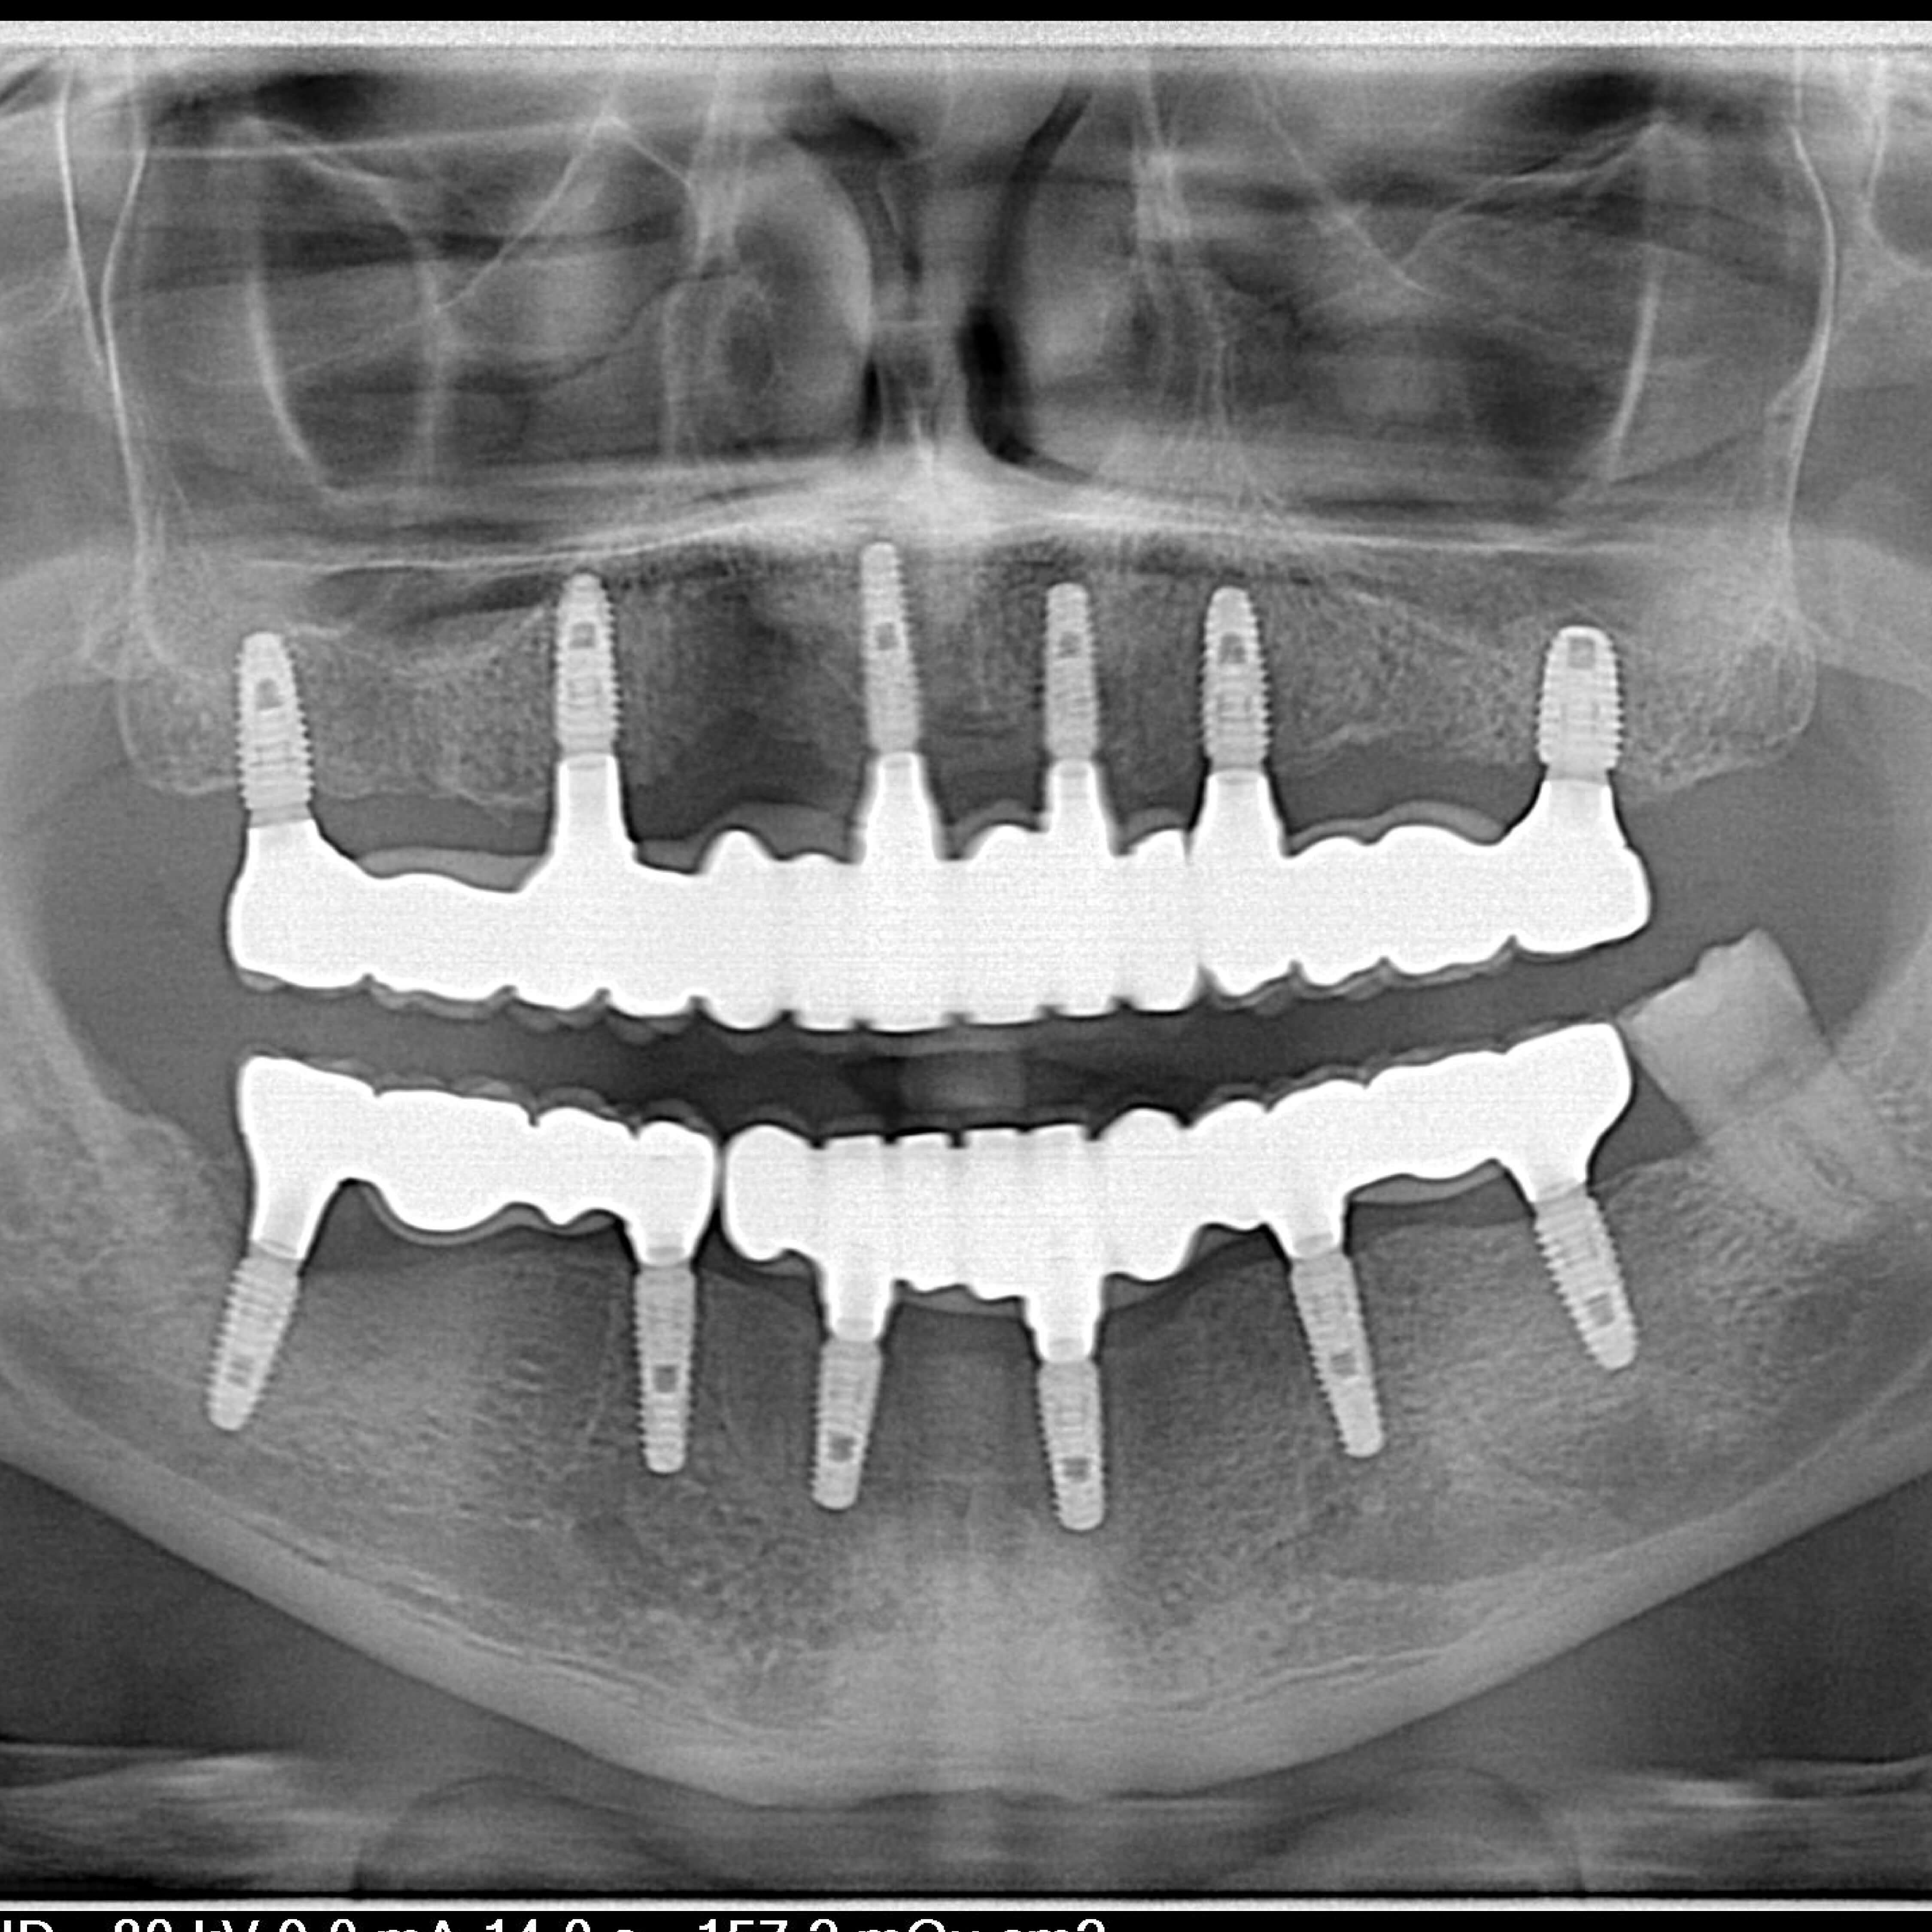

The 'All-on-4' technique involves placing four implants to support a full arch of teeth, providing a stable and immediate solution for tooth replacement.

An implant is an artificial substitute for a human tooth root, made from titanium. Titanium is a metal that is biocompatible with the human body after implantation it quickly grows close to the bone and does not cause allergic reactions. A tooth restored with an implant does not differ at all from a natural tooth.

At this stage, the implants are placed.